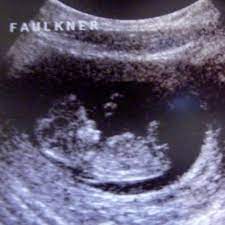

Ultraschall 9. woche. Wie gesagt hat der Gynäkologe mit dem Ultraschall eine sehr gute Möglichkeit alles bis zur letzten Schwangerschaftswoche optimal verfolgen zu können. Ihr Baby wird in der 9. Die Anlage der Ohren ist jetzt zu erkennen.

Zwischen der 9. SSW Baby Mama Untersuchung. In seltenen Fällen kann es vorkommen dass in den ersten Wochen nur eine leere Fruchthöhle auf dem Ultraschallbild zu sehen war.

Den ersten Ultraschall hatte ich vaginal und der Zweite war dann über den Bauch. SSW lassen sich auf dem Ultraschallbild inzwischen Zehen erkennen. Auch die Arme sind deutlich gewachsen und biegen sich bereits an den Ellenbogen.

Der Kiefer ist nun entwickelt. Langsam sieht es auch wie ein richtiges Baby aus. Die Beine sind länger geworden und in der 9.

Die Beine sind länger geworden und in der 9. Mit der ersten Vorsorgeuntersuchung in der 9. Auch die Nasenöffnung und die Ohren sind in der 9.

SSW gut zu erkennen genauso wie die Oberlippe und eine starke Pigmentierung der Augen. Das Baby schlägt nun Purzelbäume zappelt und schwimmt in der Fruchtblase.

Die Beine sind länger geworden und in der 9. Schwangerschaftswoche steht die erste große Vorsorgeuntersuchung mit Ultraschall an. Schwangerschaftswoche fällt es vielen Vätern leichter sich auf die veränderte Lebenssituation einzulassen. Die SSL Scheitel-Steiß-Länge beträgt nun 1722 mm. Der Kiefer ist nun entwickelt. Dabei wird das Baby erstmals ausführlich im Ultraschall vermessen. Dieser Zeitraum ist überaus wichtig für die Entwicklung der Arme und Beine.